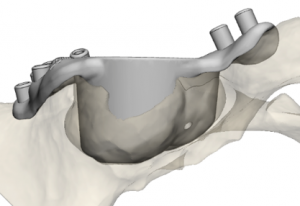

Es treballarà amb una mostra prevista de 180 pacients d’entre 18 i 80 anys dels set centres implicats, i aquests es dividiran en dos grups: un grup experimental tractat amb cirurgia digital 3D i un grup control tractat amb cirurgia convencional. Els procediments quirúrgics estudiats seran l’osteotomia de radi, una tècnica utilitzada per corregir malformacions del radi; l’artroplàstia acetabular de maluc, per tractar el desgast del maluc mitjançant la substitució dels components de l’articulació; i l’artròdesi de columna, que fusiona les vèrtebres per tractar dolor causat per fractures o malalties degeneratives.

Procés per tractar l’artroplàstia de maluc amb cirurgia digital 3D, des de la planificació digital 3D a la impressió 3D per crear un producte sanitari personalitzat.

En aquest sentit, segons afirma Fillat, la tecnologia 3D ha guanyat pes, especialment en cirurgia ortopèdica i traumatologia, perquè “permet crear models anatòmics exactes i guies quirúrgiques personalitzades a partir de les imatges del pacient, i simular digitalment el procediment quirúrgic, millorant la precisió i reduint els marges d’error”.